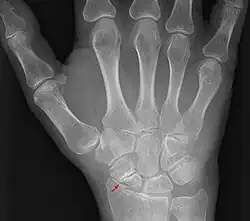

Eine Kahnbeinpseudarthrose ist eine Pseudarthrose vom Os scaphoideum des Handgelenks.

Das Kahnbein ist der biomechanisch wichtigste Knochen der Handwurzelknochen. Eine Kahnbeinpseudarthrose kann beim Ausbleiben der Bruchheilung einer Fraktur des Kahnbeines entstehen. Bei der konservativen, nicht operativen Behandlung werden Pseudarthroseraten von 23 % berichtet,[3] bei der operativen Behandlung wird in der Literatur von Pseudoarthroseraten zwischen 5 und 15 % berichtet.[4] Die Kahnbeinpseudarthrose hat somit im Wesentlichen zwei Ursachen:

- Die Kahnbeinfraktur bleibt unerkannt, da sie im Röntgen nicht vom behandelnden Arzt erkannt wird, oder der Patient nicht ins Spital ging.

Die Symptome sind Schmerzen am Handgelenk, insbesondere der sog. Tabatière oder an der Handwurzel generell. Im weiteren Verlauf kann sich auch eine Arthrose entwickeln.